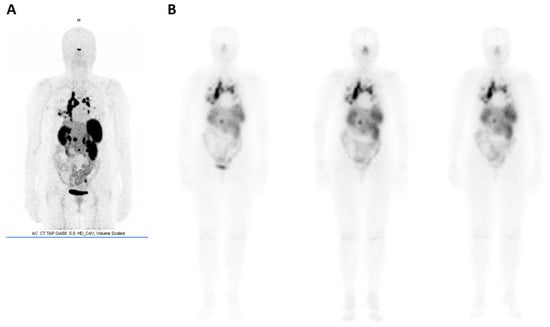

- Pfeifer, A.; Knigge, U.; Binderup, T.; Mortensen, J.; Oturai, P.; Loft, A.; Berthelsen, A.K.; Langer, S.W.; Rasmussen, P.; Elema, D.; et al. 64Cu-DOTATATE PET for Neuroendocrine Tumors: A Prospective Head-to-Head Comparison with 111In-DTPA-Octreotide in 112 Patients. J. Nucl. Med. 2015, 56, 847–854. [Google Scholar] [CrossRef]

- Johnbeck, C.B.; Knigge, U.; Loft, A.; Berthelsen, A.K.; Mortensen, J.; Oturai, P.; Langer, S.W.; Elema, D.R.; Kjaer, A. Head-to-head comparison of 64Cu-DOTATATE and 68Ga-DOTATOC PET/CT: A prospective study of 59 patients with neuroendocrine tumors. J. Nucl. Med. 2017, 58, 451–458. [Google Scholar] [CrossRef]

- Andersen, T.L.; Baun, C.; Olsen, B.B.; Dam, J.H.; Thisgaard, H. Improving Contrast and Detectability: Imaging with [55Co]Co-DOTATATE in Comparison with [64Cu]Cu-DOTATATE and [68Ga]Ga-DOTATATE. J. Nucl. Med. 2020, 61, 228–233. [Google Scholar] [CrossRef] [PubMed]

- Hicks, R.J.; Jackson, P.; Kong, G.; Ware, R.E.; Hofman, M.S.; Pattison, D.A.; Akhurst, T.A.; Drummond, E.; Roselt, P.; Callahan, J.; et al. 64Cu-SARTATE PET Imaging of Patients with Neuroendocrine Tumors Demonstrates High Tumor Uptake and Retention, Potentially Allowing Prospective Dosimetry for Peptide Receptor Radionuclide Therapy. J. Nucl. Med. 2019, 60, 777–785. [Google Scholar] [CrossRef] [PubMed]